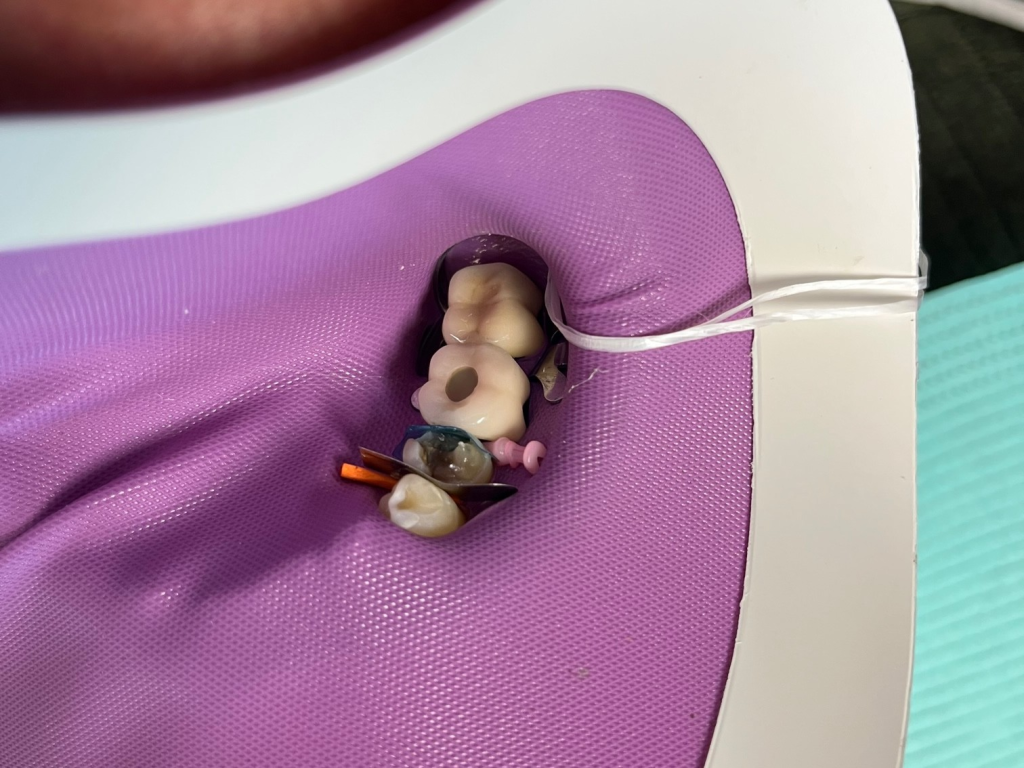

Broken tooth with DentXpinTM repair.

7